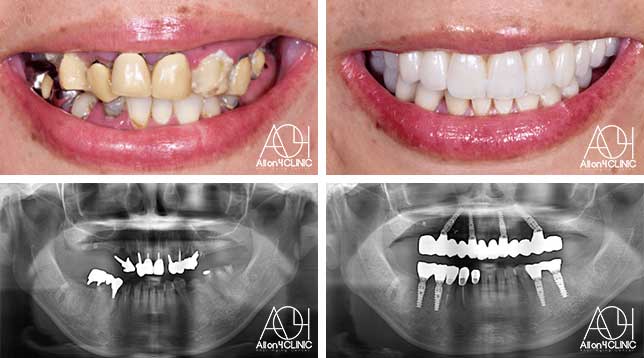

Treatment : All-on-4 zygoma

- Upper All-on-4

- Lower All-on-4

Age : 65 Sex : 男 H.M

| 主訴 | 日本各地のクリニックを受診し、カウンセリングを何回も受けているがどのクリニックで治療を受けるべきか迷っている。 |

| 治療内容 | ガイデッドサージェリーにてインプラント埋入。骨量が少量であったためザイゴマインプラントにて治療 |

| 治療費(総額) | ¥5,200,000(税抜) 『モニター割引適用』 『オリジナル動画撮影協力あり』 |

| リスク | 治療後の口腔管理が不適切な場合、埋入したインプラント周囲に感染・炎症を起こし、脱落する可能性がございます。 |